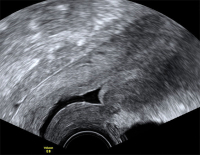

Tipps und Tricks im Gyn-Ultraschall: Die Sectionarbe am nichtschwangeren Uterus und in der Frühschwangerschaft

Journal für Gynäkologische Endokrinologie 2014; 8 (2) (Ausgabe für Österreich): 22-24 Journal für Gynäkologische Endokrinologie 2014; 8 (2) (Ausgabe für Schweiz): 24-26 Volltext (PDF) Abbildungen